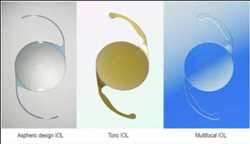

Demanda del mercado mundial de lentes intraoculares, pronóstico de ingresos y oportunidades interesantes de 2022 a 2028

Zion Market Research ha publicado el último informe sobre el » mercado Lente intraocular » global. Los detalles sobre el mercado Lente intraocular se han actualizado completamente con información completa …